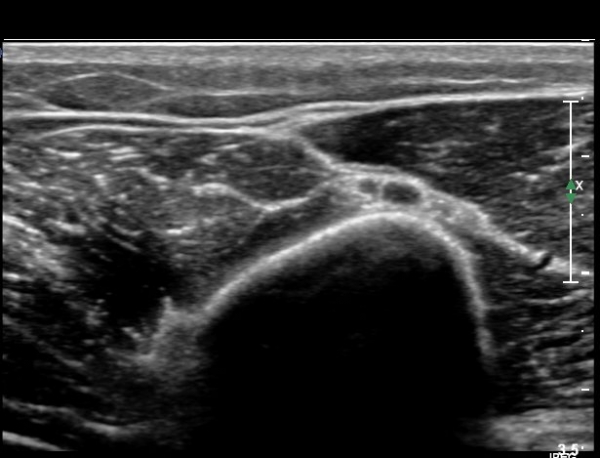

ŽÃÊÀÚ¸¦ Á¶±Ý ´õ ¸»´ÜÀ¸·Î À̵¿ÇÏ´Ï ¿ä°ñ½Å°æÀÌ °üÂûµÇÁö ¾Ê°í(»çÁø3),

Á¶±Ý ´õ ¸»´ÜÀ¸·Î À̵¿ÇÏ´Ï ´Ù½Ã Àú¿¡ÄÚ ºÎÁ¾ »óÅ·Π°üÂûµÈ´Ù(»çÁø 4).